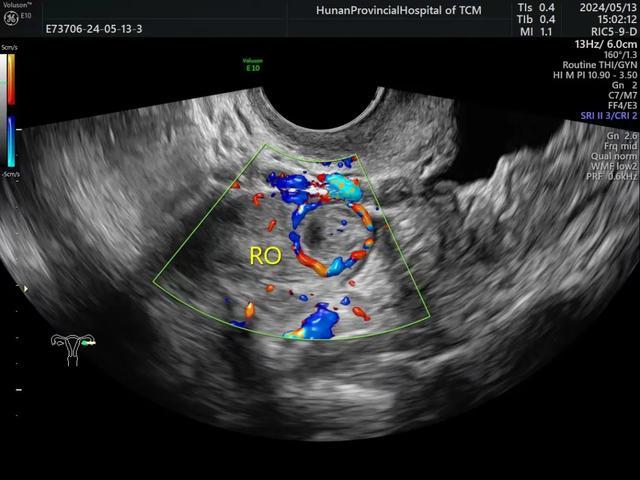

2、黄体囊肿:

①多样性:大多数可归纳为囊性、囊实性、实性3种类型。

② 多变性:同一黄体囊肿在不同的时期其超声表现有很大的变化。

③ 黄体囊肿为功能性囊肿,除非破裂否则无手术指征。

④CDFI:部分囊肿的周边可见典型的环状或半环状血流,黄体血流一般在排卵后1-2天出现,一周左右达高峰,频谱显示为低阻血流。